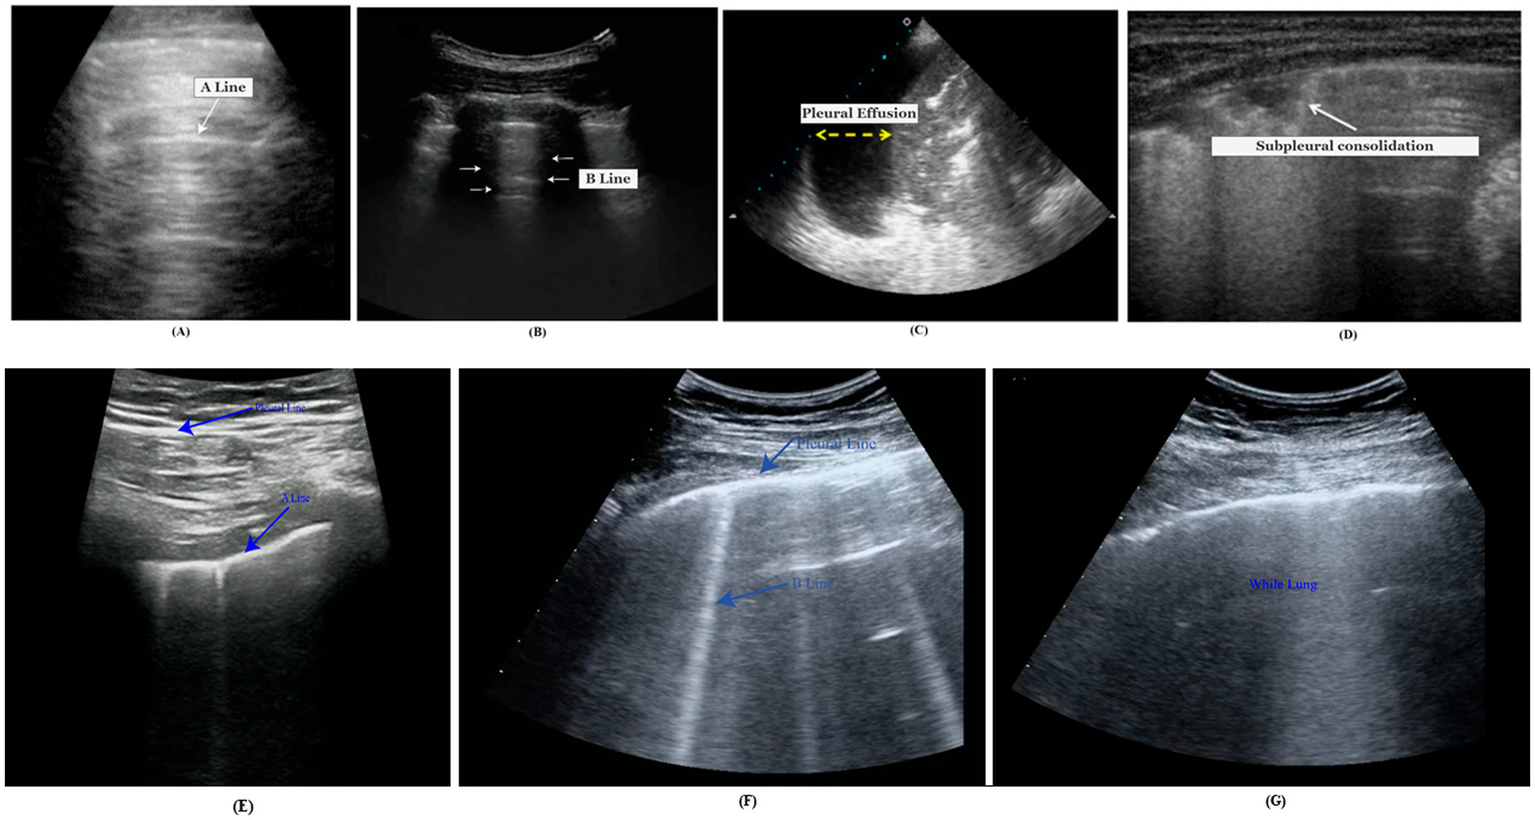

LUS has become increasingly popular for detecting lung diseases due to its inherent convenience, absence of ionizing radiation, and notable accuracy. LUS differs from other ultrasound examinations in that it is mainly artifact-based. Several artifacts or abnormal results in LUS can distinguish between normal and infected lungs. Below is an explanation of a few of the artifacts.

3.1 A line

A-lines are bright, slowly diminishing horizontal lines placed at equal intervals beneath the pleural line that indicates the repeated artifact of the parietal pleura (Bard, 2021). The gap of A-lines is nearly identical to the gap between the skin surface and the pleural line. Alines are most visible in the normal lung because they are caused by air gas beneath the pleura (Bard, 2021). Figure 1A demonstrates the A-line of the lungs.

3.2 B line

B-lines, called LUS comets, are caused by separate vertical reverberation artifacts starting at the pleural line, extending throughout the image without intensity reduction, and moving synchronously with lung sliding (Ostras et al., 2021). Their distinguishing feature is that they conceal A-lines. Normal lungs may have diffused B-lines (less than two in each intercostal space). They are considered severe if three or more B-lines are seen in a single image within two ribs. The quantity of B-lines is strongly related to disease severity.

In Figure 1B, the B-lines conceal the horizontal Alines visible in the neighboring intercostal space (represented by an asterisk).

3.3 Pleural effusion

A pleural effusion is a fluid in the pleural cavity that appears as a dark, hypoechoic, or anechoic area (de Groot et al., 2023). An ultrasound video clip captures the lateral motion between the lung and the chest cavity during respiration. An infrequent finding in COVID-19 is pleural effusion, which usually arises from a coexisting disease. Ultrasound is a highly dependable pleural effusion detection, measurement, and follow-up technique (de Groot et al., 2023). A pleural effusion is represented by the yellow arrow in Figure 1C.

3.4 Consolidations

When the air content in lung tissue falls below 10% of regular lung aeration, the pleural line is disrupted, and consolidative lesions occur (Soldati et al., 2020). Consolidations are more common in the lower posterior regions of patients with COVID-19 pneumonia, are often multiple, and may appear with or without air bronchograms. In Figure 1D, a B-line (dot) is illustrated with subpleural consolidation (arrow).

A normal LUS shows the pleural line as a continuous and consistent structure. Horizontal A-lines or fewer than two vertical B-lines are frequently observed. In ultrasound imaging, this pattern reflects the lung’s healthy state. Scattered B-lines are the most common US findings for diagnosing COVID-19. Pleural line irregularities and subpleural consolidations are the most likely findings, while pleural effusion is less frequent. In COVID-19 pneumonia, interstitial patterns, pleural abnormalities, and consolidations are the most typical LUS findings. These abnormalities typically have a bilateral, inconsistent distribution and clearly defined spared regions. The most common sign of severe COVID-19 pneumonia is a “white lung” that is entirely diffused with B-lines. Identifying COVID-19 pneumonia from other illnesses may be made easier using B-lines.

In clinical practice, LUS is being used more frequently to treat other diseases such as infection, asthma, pulmonary edema, pulmonary fibrosis, and pneumothorax. As in the case of interstitial lung disease/pulmonary fibrosis and acute respiratory distress syndrome (ARDS), the pleural line frequently appears thickened, irregular, or broken in affected areas. There will be an irregular hyperechoic line at the interface between the consolidated pathological lung and the aerated healthy lung. A focal subpleural hypoechoic region could be an indication of a minor infection. B-lines and pleural effusions define pulmonary edema. Irregular thickening of the hyperechoic pleural line is seen in asthma LUS. The lung point is where the pneumothorax and normal lung meet. Identifying a lung point on LUS allows for attaining 100% specificity in diagnosing pneumothorax. In the Figure 1 comparison, (E) represents normal LUS, (F) COVID-19 indicative lung, and (G) white lung for severe COVID-19 pneumonia. LUS findings in COVID-19 pneumonia are similar to those seen before the COVID-19 era. Common ultrasound symptoms, such as multiple B-lines, consolidations, and pleural line irregularities, emphasize the remarkable resemblance between the two diseases.